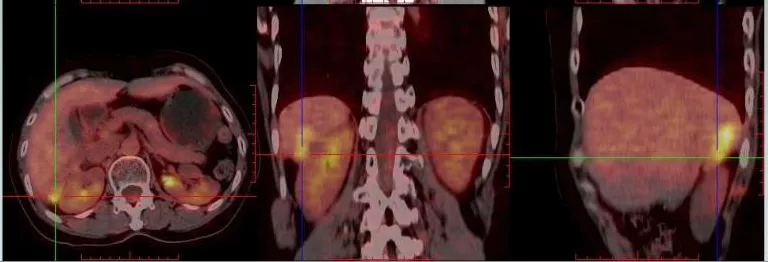

2016.10.14查PET-CT: 盆腔内软组织密度灶,FDG代谢异常增高,考虑转移灶;右肝后下段包膜处结节样、片状转移灶;左肾前方斑片状,腹主动脉管壁处(L3椎体水平)FDG代谢轻度增高,考虑肿瘤活性组织存在。

PET-CT检查结果